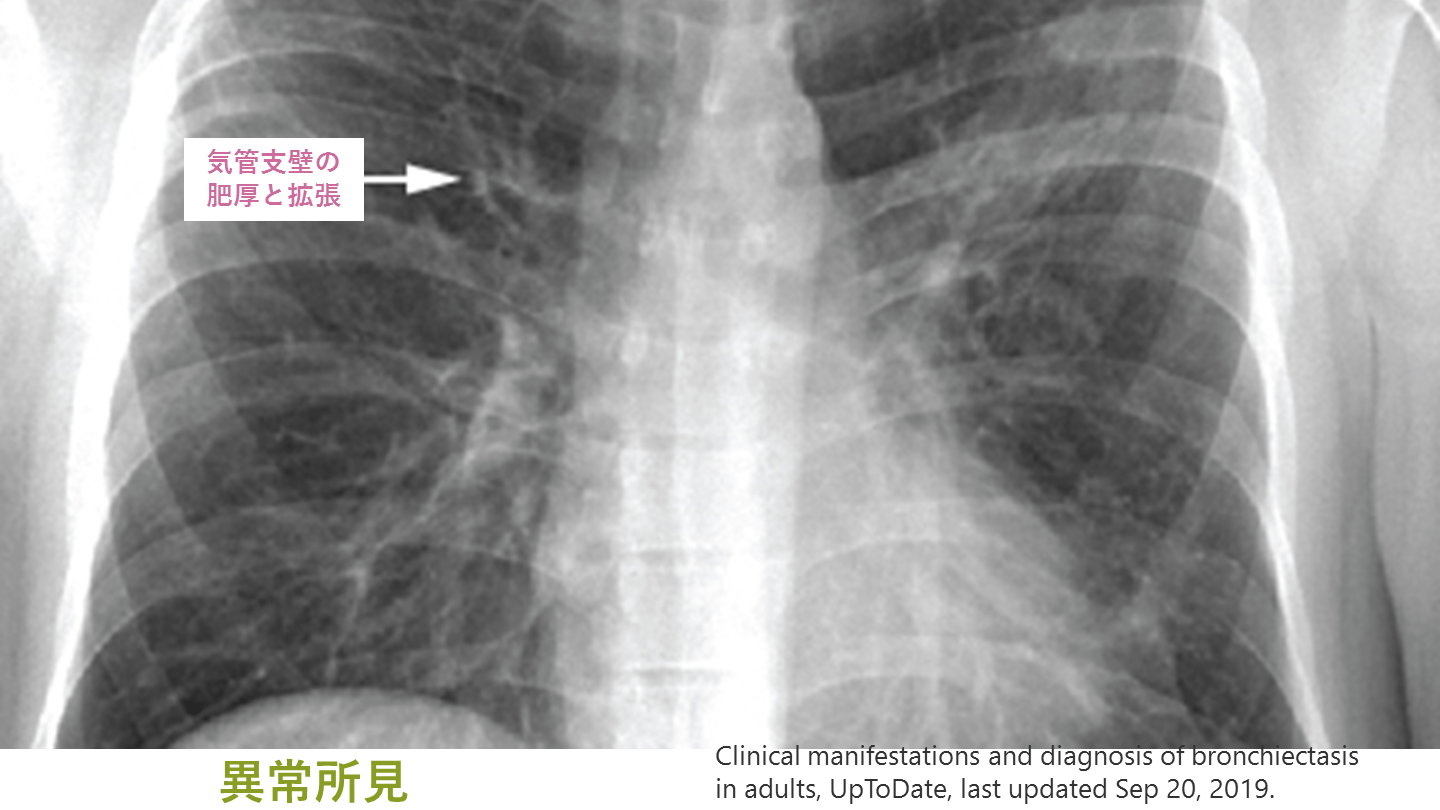

レントゲンで注意すべき所見 多くの気管支拡張症症例では異常像を示す 異常所見(単独で確定診断はできない) 線状無気肺 気管支の肥厚・拡張 不整な末梢陰影(粘液栓を示唆) Clinical manifestations and diagnosis of bronchiectasis in adults, UpToDate, last updated Sep 20, 2019.

#14.

異常所見 Clinical manifestations and diagnosis of bronchiectasis in adults, UpToDate, last updated Sep 20, 2019. 気管支壁の 肥厚と拡張